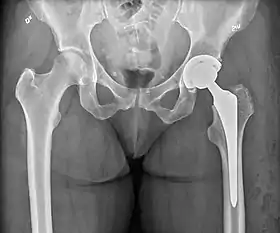

Post-operative projectional radiography is routinely performed to ensure proper configuration of hip prostheses.

The direction of the acetabular cup influences the range of motion of the leg, and also affects the risk of dislocation.[9] For this purpose, the acetabular inclination and the acetabular anteversion are measurements of cup angulation in the coronal plane and the sagittal plane, respectively.

Center of rotation: The horizontal center of rotation is calculated as the distance between the acetabular teardrop and the center of the head (or caput) of the prosthesis and/or the native femoral head on the contralateral side.[80] The vertical center of rotation instead uses the transischial line for reference.[80] The parameter should be equal on both sides.[80]